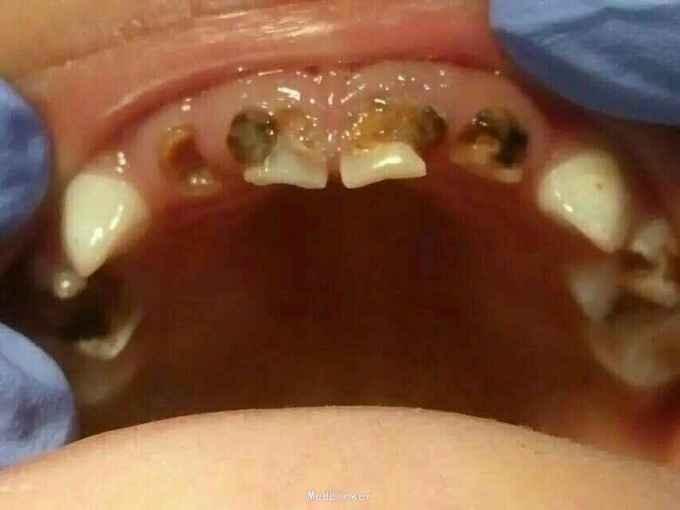

患者,男,3岁半 主诉:近一年前牙有洞影响美观,现要求修复(母述) 现病史:患者自幼前牙颜色发育异常,幼时含奶瓶睡觉的习惯,近一年前牙出现大小不一的龋坏,影响美观,现要求修复

检查:51,61颈部环形龋,龋坏和龈缘齐平,色黑,质软,颊侧龋坏已达髓腔,无明显松动,冷热(-),叩(-),其他无异常 X线片示:牙根未吸收,根尖无暗影,其余无异常

诊断:51,61奶瓶龋 治疗计划:51.61rct+乳前牙透明冠修复 治疗: 1.51.61去软龋,行rct(见图1) 2.metapex根充,丁氧膏暂封(见图2.5) 3.乳前牙透明冠修复(见图3.4.)